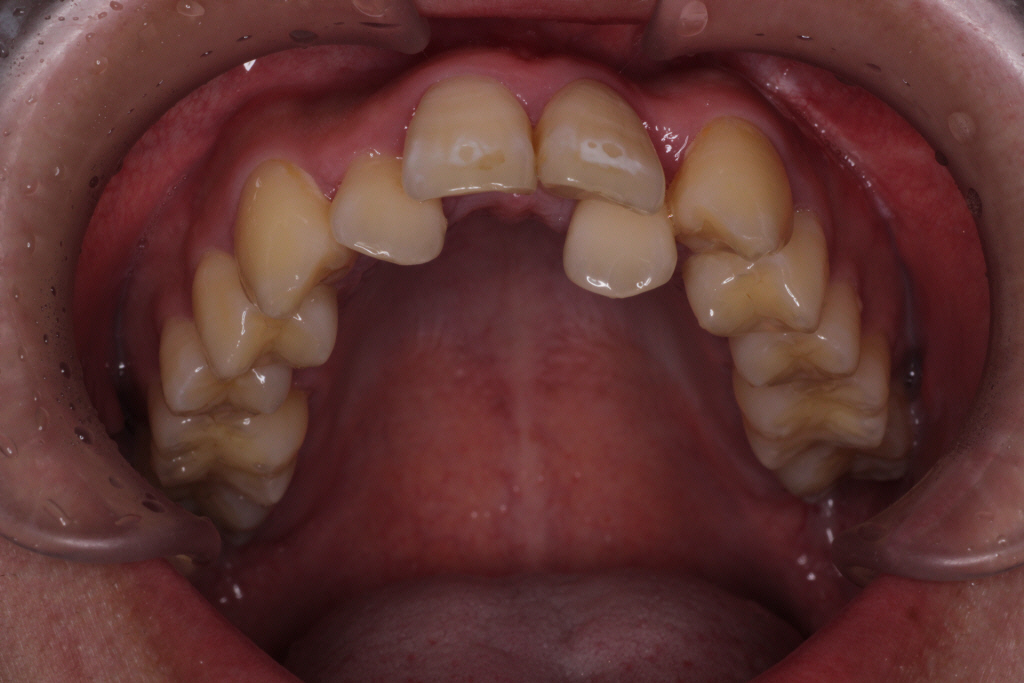

日本人は特に上顎の一番目の歯に比べて著しく二番目の歯が小さいことが多いです。(下図)

さらに二番目の歯が一番目の歯よりも後ろに生えてきて一番に隠れていることも多いです。(下図)

そうなると、歯の重なりによってアタッチメントのつけれる場所が限定されます。

また、歯が重なっているとその歯だけをアライナーで囲い込むことができず、